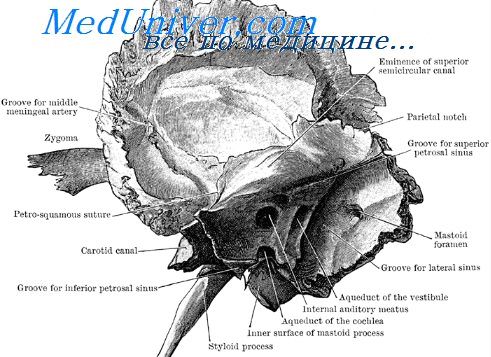

Анатомия и особенности фиссуры петротимпаника